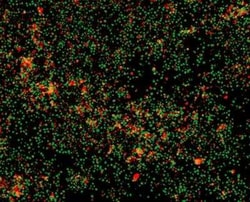

Novus Biologicals™ Propidium Iodide